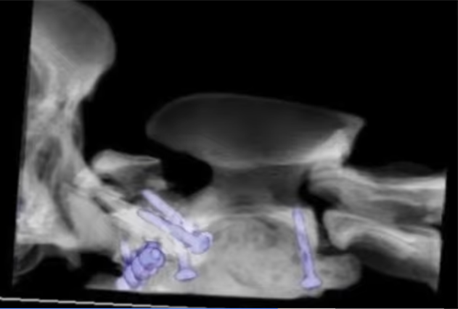

A combination of SOP plate, screws and bone cement were carefully used - with great precision - to realign and stabilise Poppy’s fracture. She was then hospitalised in high dependency unit for several days.